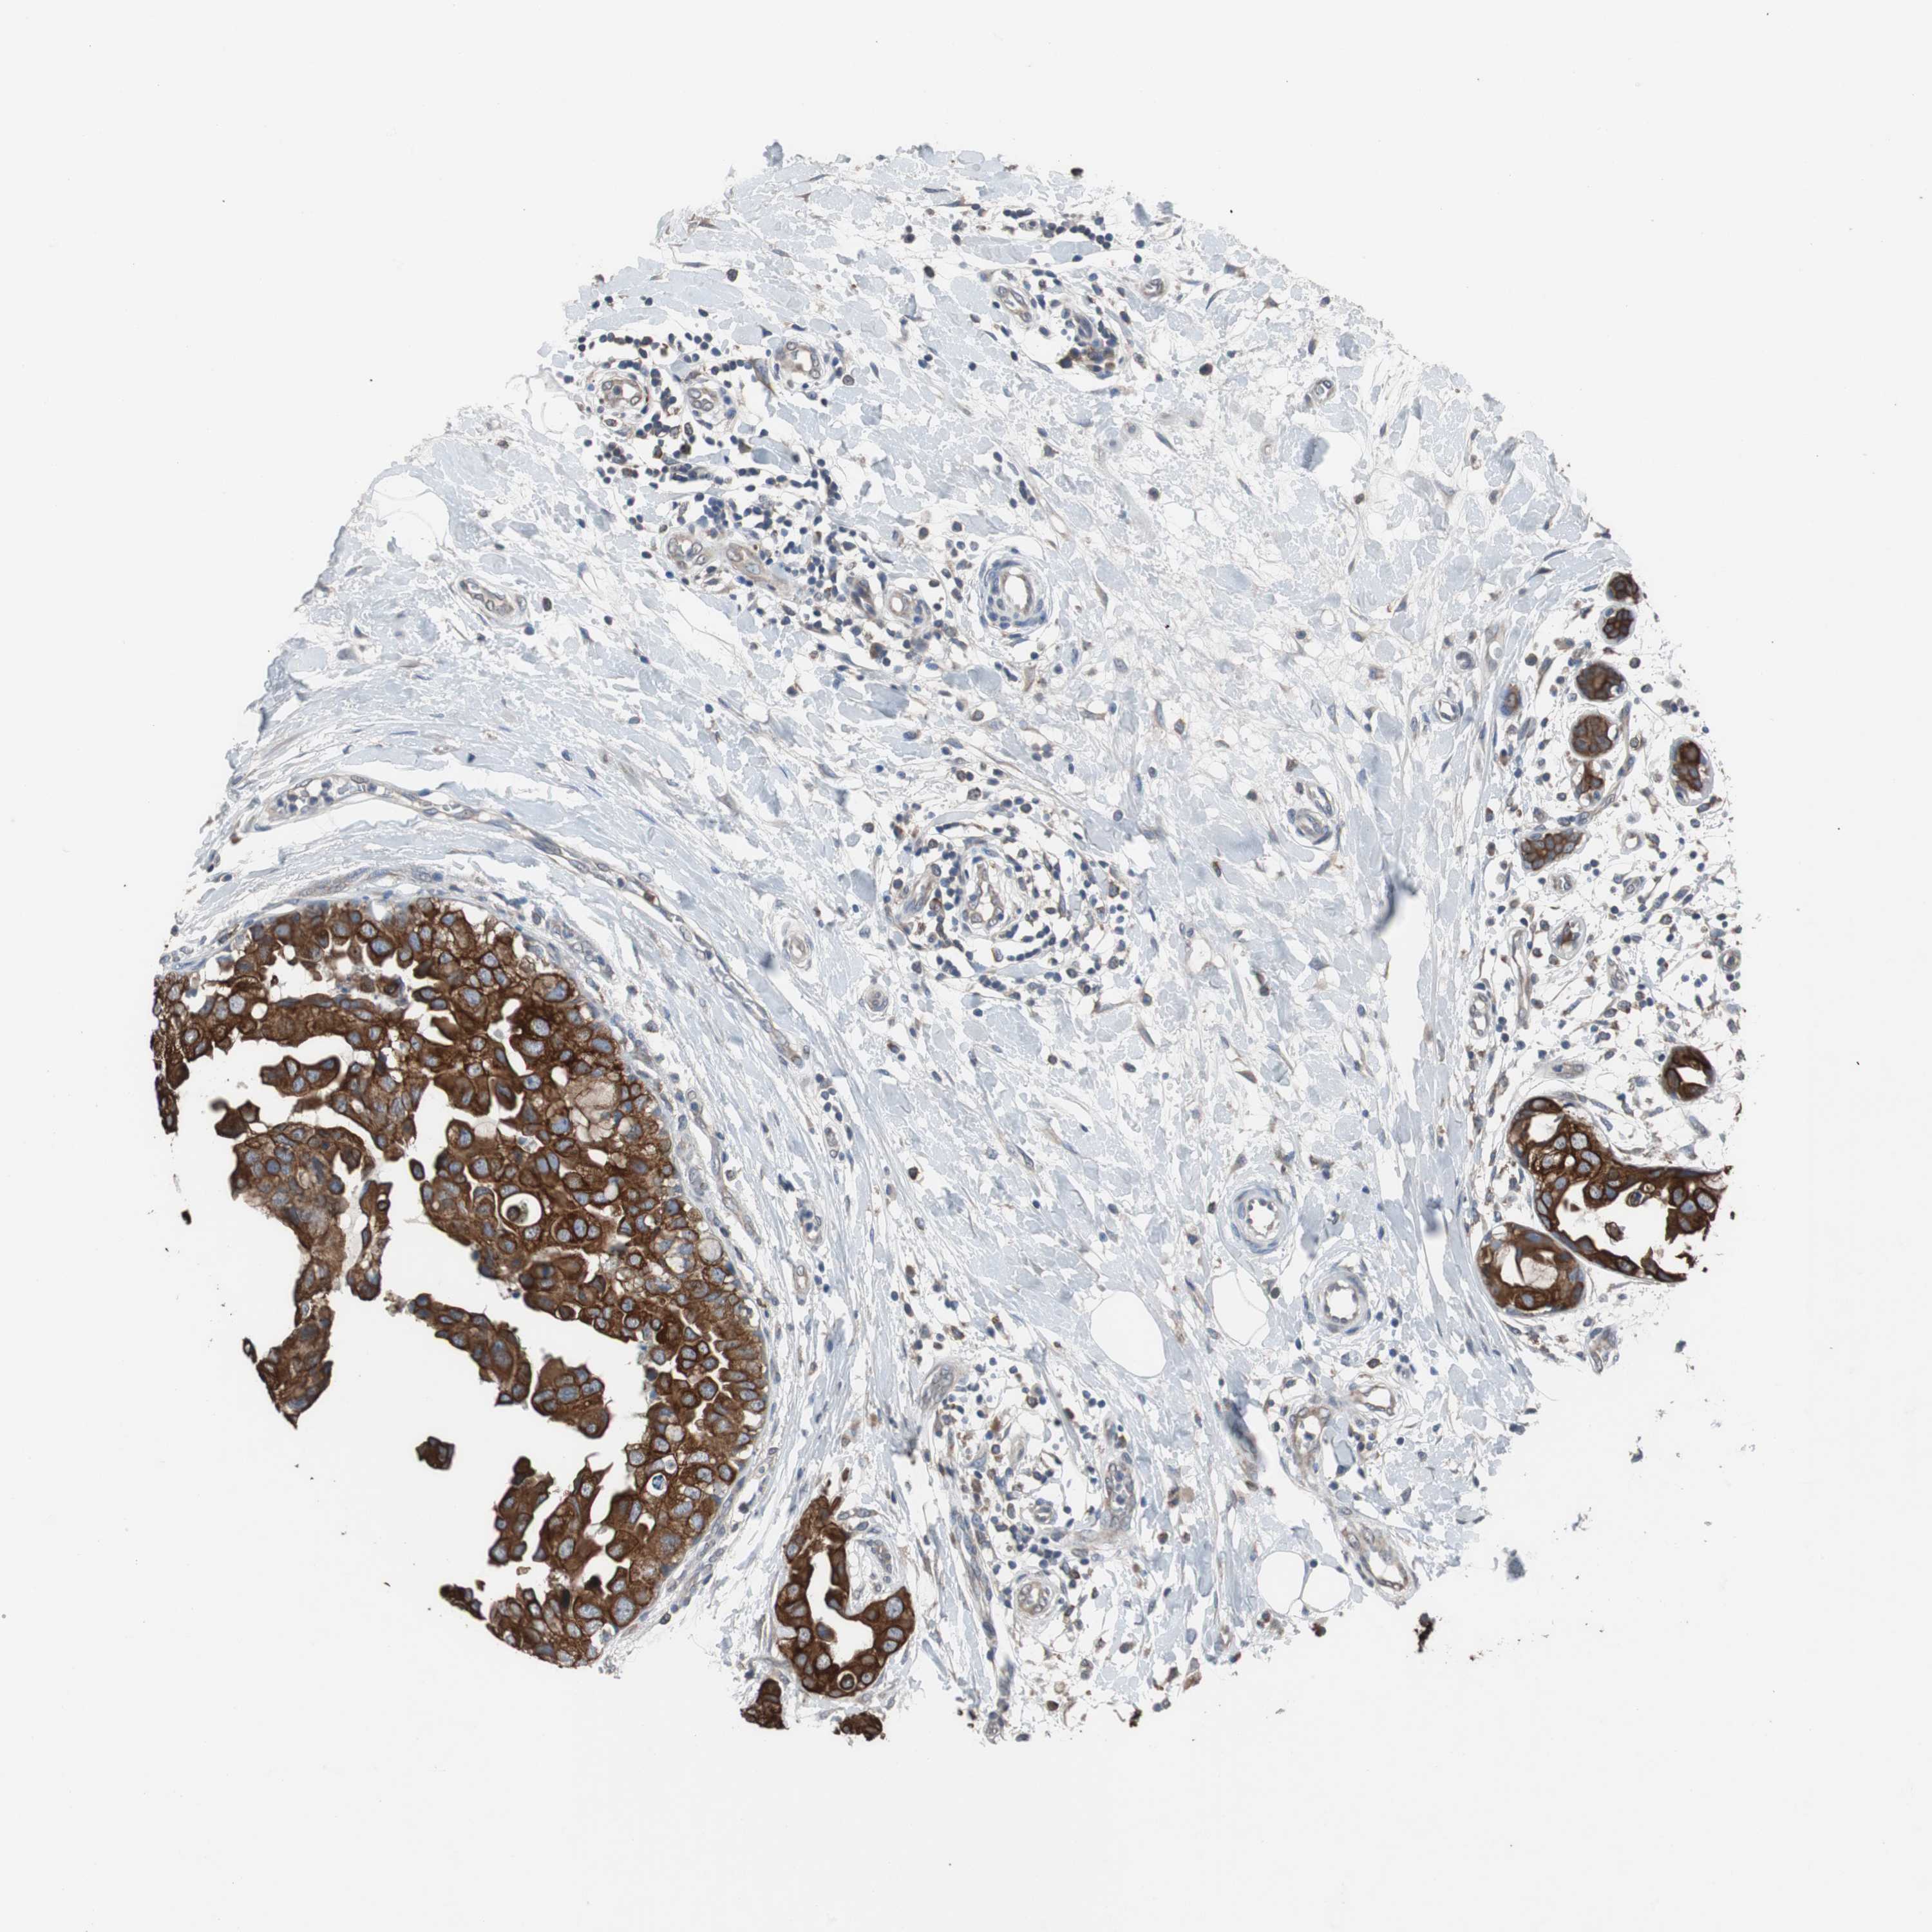

CANCER BREAST CANCER Show tissue menu

BRCA TCGA BRCA VALIDATION PROTEIN EXPRESSION

ANTIBODIES

AND

VALIDATION